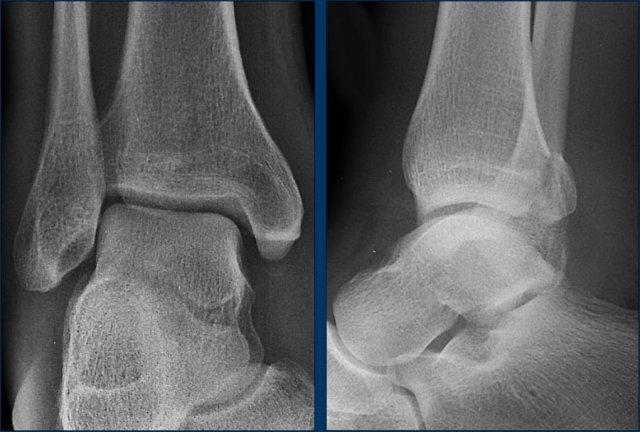

Ca 3 – Chấn thương cổ chân

Hình ảnh cho thấy những dấu hiệu gì?

Phân độ tổn thương trong trường hợp này là gì?

Nhấp vào hình ảnh để xem phóng to.